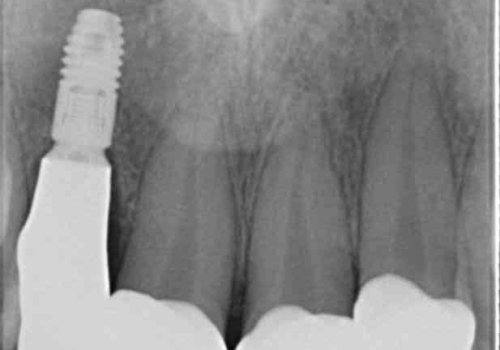

- 虫歯の治療を繰り返した前歯の見た目の改善を求めて来院されました。

大きく詰められたコンポジットレジンと虫歯の再発が見られ、経年劣化により審美性も損なわれていました。

充填されたコンポジットレジン・再発した虫歯を神経に影響が出ないよう丁寧に除去し再充填をしたのちオールセラミッククラウンで前歯の審美性を回復します。

※右上2のインプラント治療は他院のものです。